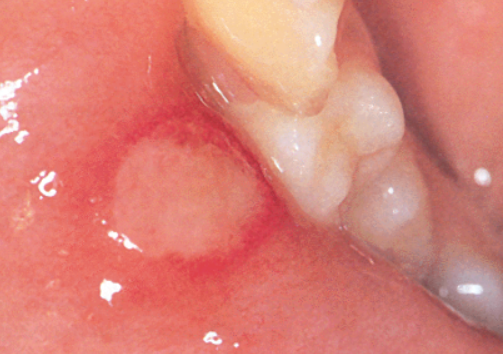

2. 면역력 저하로 인한 아프타성 궤양

- 흔히 “입병”이라 부르는 아프타성 궤양은 피로, 스트레스, 수면 부족, 면역력 저하 시 잘 생깁니다.

- 초기에 작은 수포처럼 시작되며, 이내 하얗게 짓무른 궤양 형태로 변함

- 통증은 심하지만 전염되지 않으며, 보통 7~10일 내 자연치유

❗ 주의: 한 달에 2회 이상 반복된다면 면역 관련 질환 검사를 고려해야 합니다.